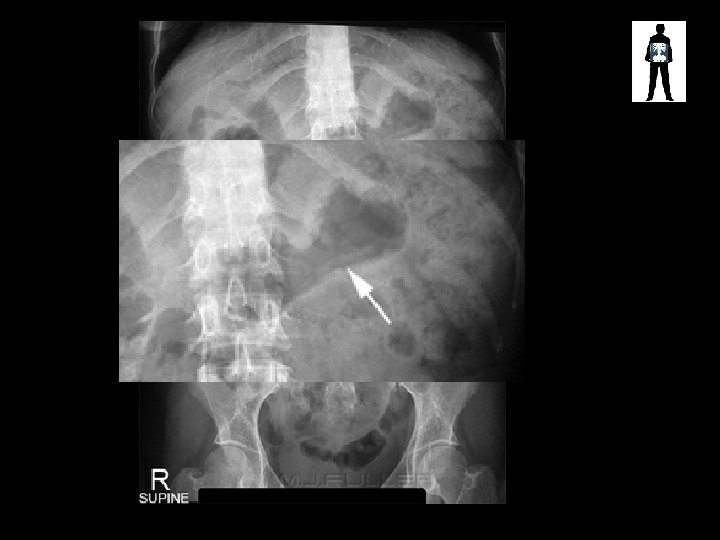

Is this okay?

Fluid Level in Stomach ERECT ABDO